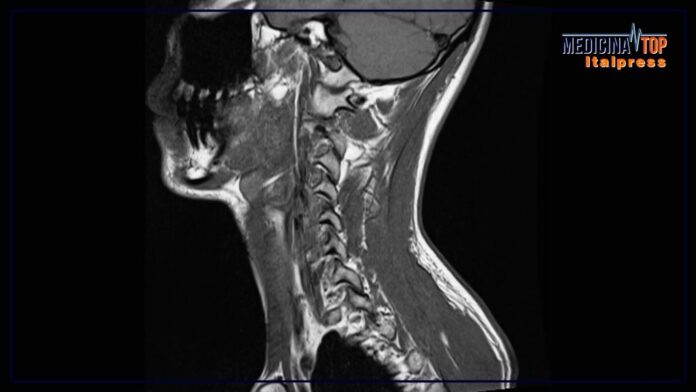

MILANO (ITALPRESS) – Negli ultimi anni si è osservato un aumento notevole dei casi di tumori all’orofaringe, che colpiscono cioè la parte centrale della gola, comprese le tonsille e la base della lingua. Solo in Italia si registrano oltre 6.000 nuovi casi ogni anno, con un aumento particolarmente significativo tra gli uomini tra i 50 e i 70 anni, e tra i giovani adulti, anche a causa di stili di vita scorretti. A livello globale, l’OMS segnala che l’incidenza di questi tumori è più alta nei paesi sviluppati, dove si stima che i tumori correlati all’infezione da HPV, il papillomavirus umano, rappresentano il 60% dei casi. Nella maggioranza dei casi, però, la prognosi è favorevole. La diagnosi precoce, insieme al continuo miglioramento delle cure e dei trattamenti chirurgici, sono gli elementi in grado di fare la differenza. Sono questi alcuni dei temi trattati da Giuseppe Mercante, professore ordinario di Otorinolaringoiatria e direttore della Scuola di specializzazione medica in Otorinolaringoiatria di Humanitas University, e referente per l’unità operativa di Otorinolaringoiatria del Gruppo Multidisciplinare Testa-Collo all’interno del Cancer Center di IRCCS Istituto Clinico Humanitas di Rozzano, intervistato da Marco Klinger, per Medicina Top, format tv dell’agenzia di stampa Italpress.

“E’ importantissimo attenzionare questo argomento, perchè negli ultimi anni abbiamo visto un aumento dei casi – ha esordito – Noi parliamo di gola, ed è una zona chiave del nostro corpo, perchè è un filtro di tante cose, è un crocevia tra la via aerea e quella digestiva. Tutto quanto viene da noi ingerito passa per l’orofaringe, cioè il distretto di tonsille e base della lingua”. Sui segnali di un possibile tumore dell’orofaringe: “Una tumefazione del collo ci deve rendere molto vigili – ha spiegato il professore – Da adulti dobbiamo stare attenti, può succedere che ci siano delle cellule tumorali partite da una mucosa della gola che vanno a localizzarsi in quelle sedi”. “Tra gli altri segni da indagare anche altri tipi di problematiche della gola che tendono a non regredire nel giro di una-due settimane – ha aggiunto Mercante – Per esempio, un dolore lancinante alla gola, e non il semplice mal di gola, magari asimmetrico e dunque localizzato su un solo lato”.